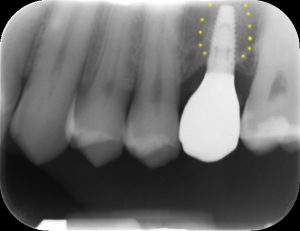

| Inadeguata quantità di osso residuo per inserire un impianto. | Con la tecnica del mini-rialzo l’impianto è stato inserito contemporaneamente al piccolo innesto di osso. |

| in giallo evidenziato il contorno della base del seno mascellare | in giallo evidenziata la porzione di osso innestato |